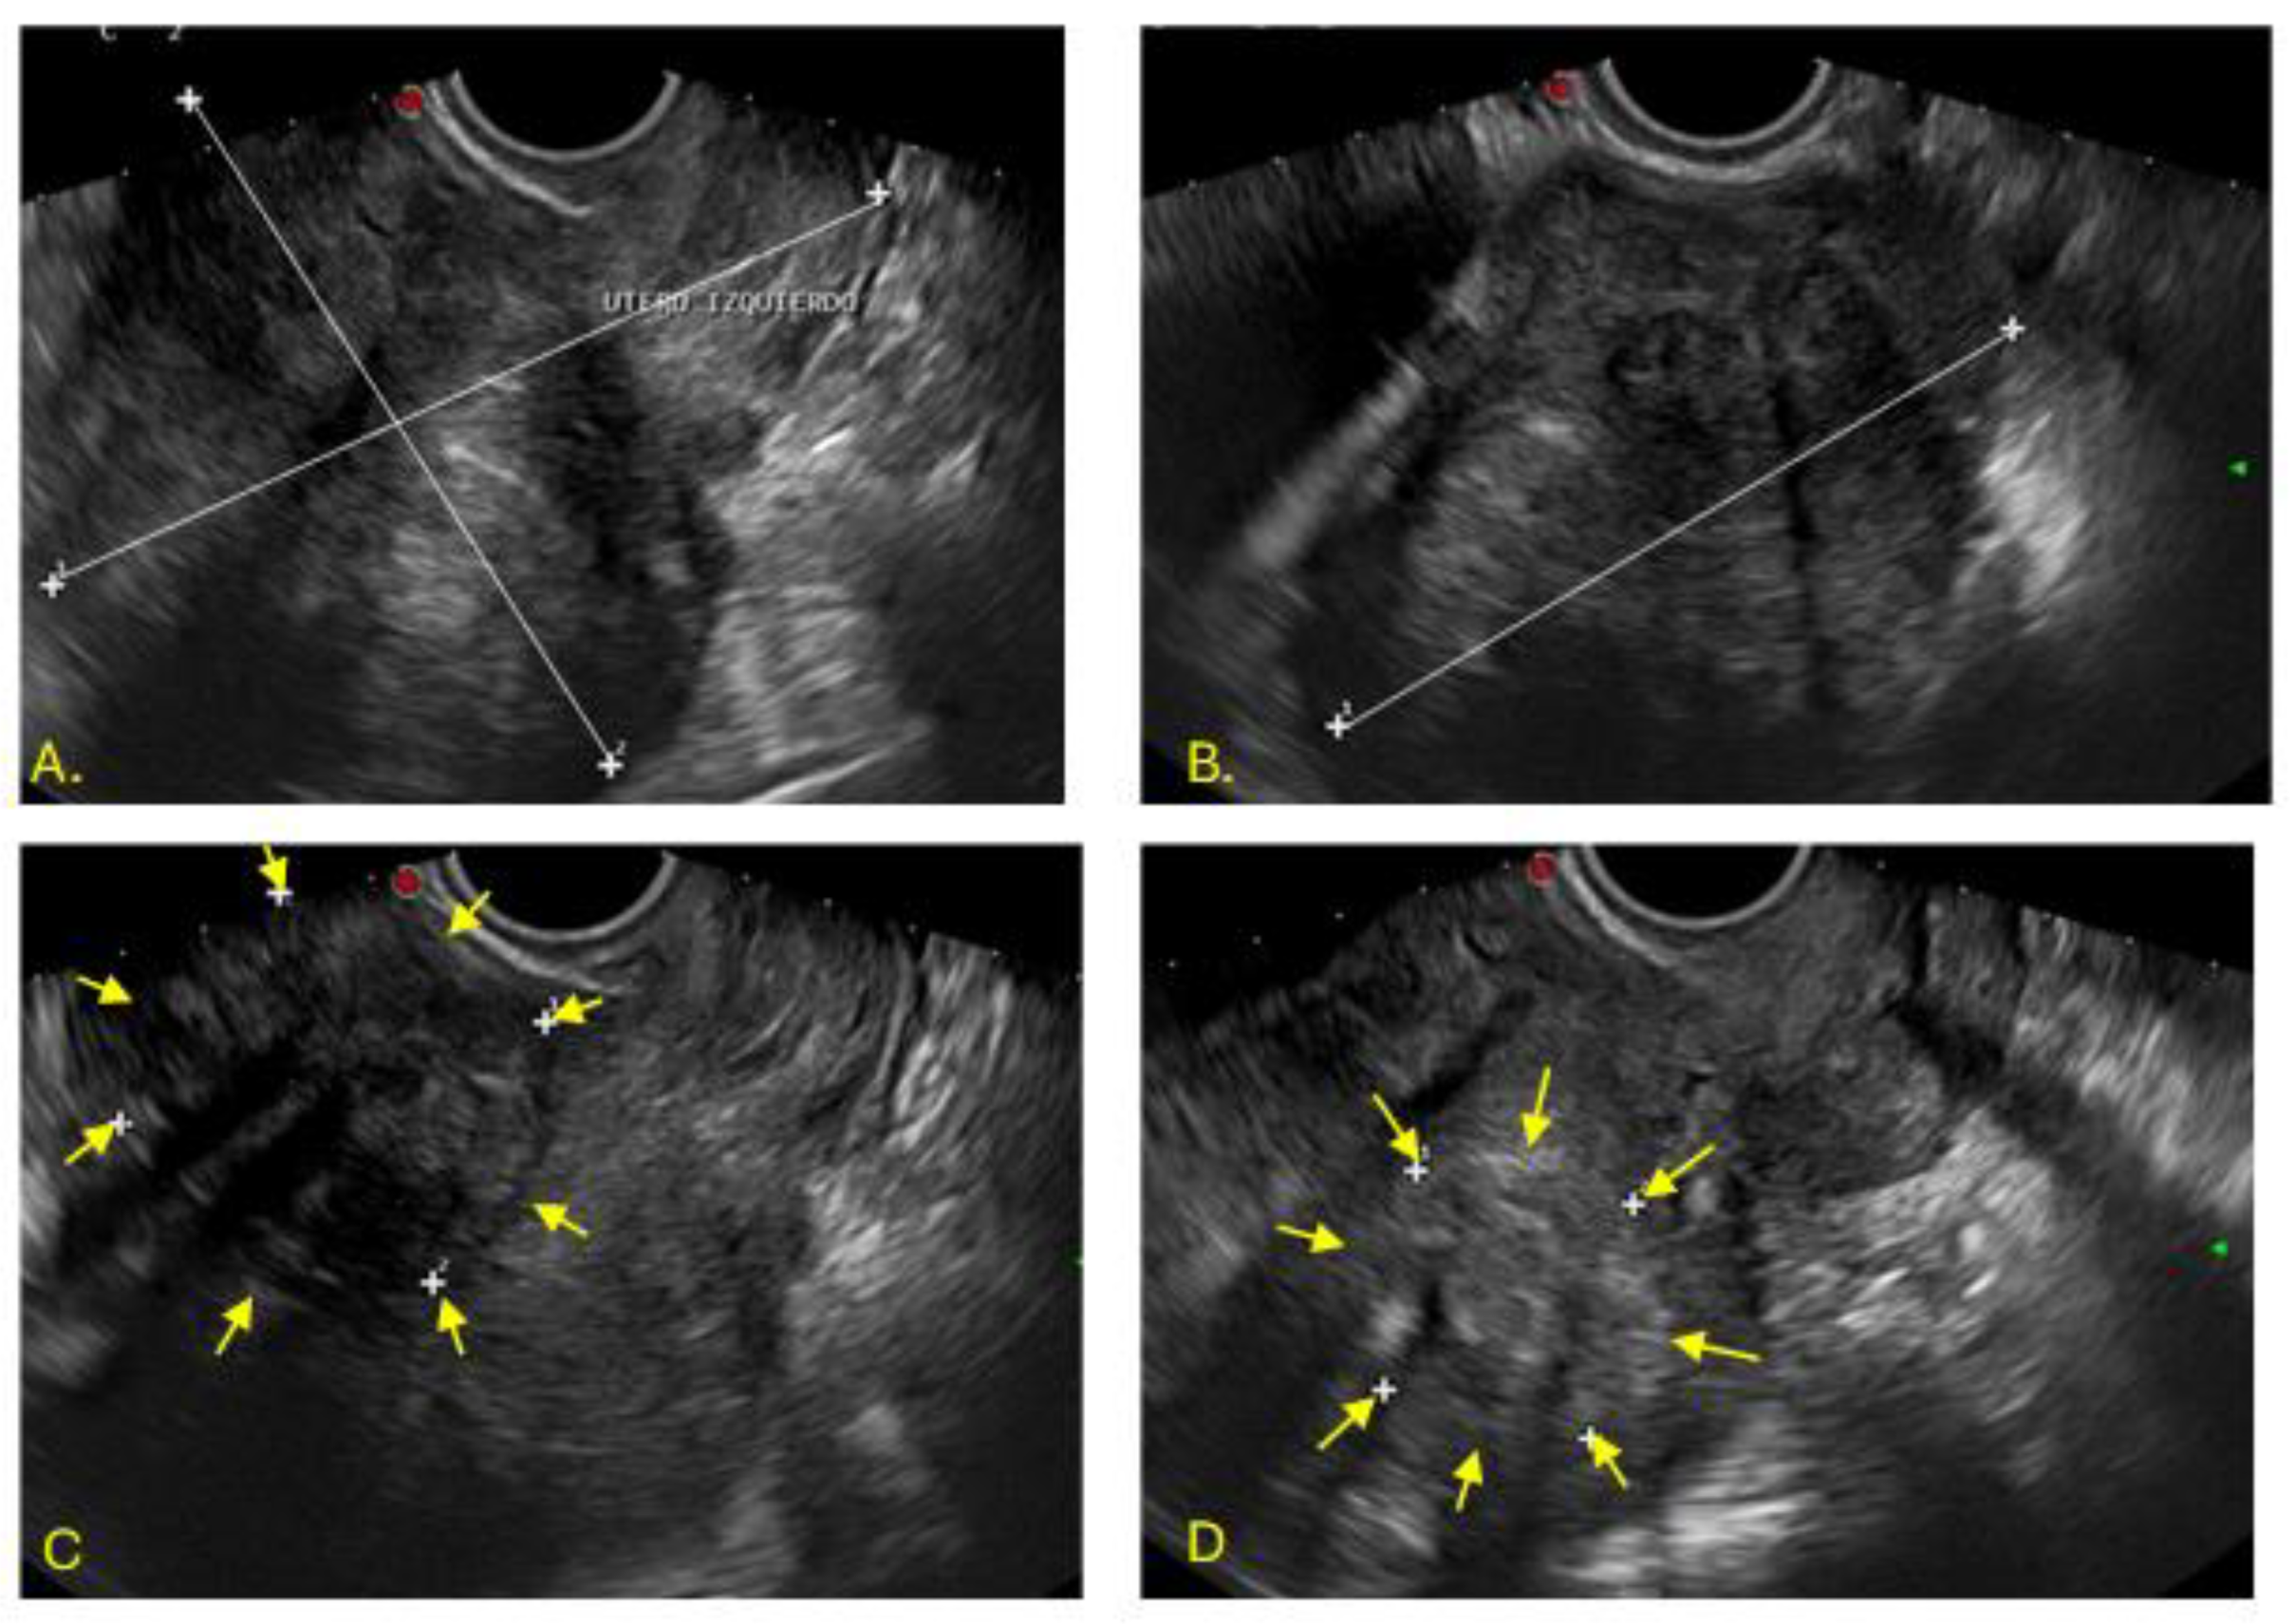

The right uterus measured 112x67x65mm, with heterogeneous myometrium and a solid submucosal nodular image of 52x49mm (FIGO 1), which caused endometrial dilation (Figure 2)

Figure 2. Endovaginal ultrasound of the right cavity. Image A: Sagittal plane of the left uterus, length 112 mm, anteroposterior diameter 67 mm. Image B: Transverse diameter 65 mm. Image C: Heterogeneous myometrium, solid nodular image measuring 52 x 49 mm in the submucosal shape.